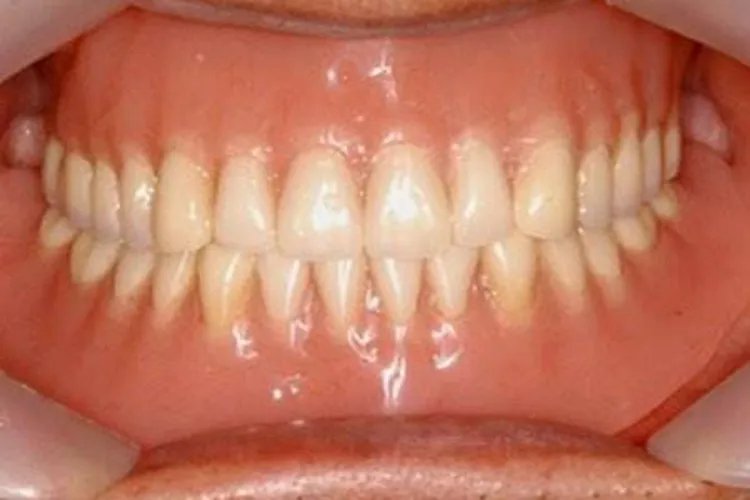

的有关信息介绍如下:概述牙槽骨是上下颌骨包围和支持牙根的部分,由牙根支撑呈凹槽状。骨质较疏松,且富于弹性,是支持牙的重要组织。形态牙槽骨是上下颌骨包围和支持牙根的部分,又称牙槽突,呈凹槽状。牙槽骨由固有牙槽骨和支持骨组成,X线片上,固有牙槽骨显示为环绕牙根的白色阻射线。容纳牙根的窝称牙槽窝,在冠方的牙槽窝的游离端称牙槽嵴。牙槽嵴的形态在前牙区为圆柱状,磨牙区为扁平状,而在颊舌侧变薄甚至消失。